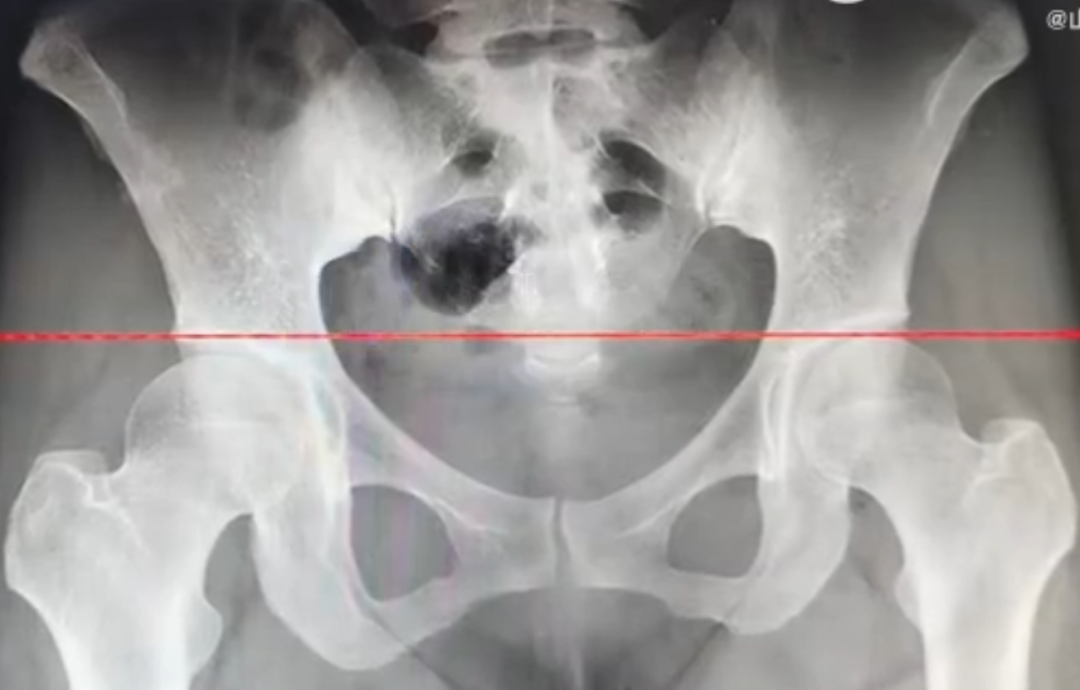

医生发现

她的两腿相差1.5厘米

医生认为

这位患者长期跷二郎腿

导致一侧骨盆上提

从而出现假性腿短的情况